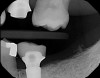

Plugging into digital workflows provides opportunities to integrate CAD/CAM technologies at every step of the treatment process for dental implants. In another example, a patient presented with a failing tooth No. 8 (Figure 6 and Figure 7). After discussing treatment options, the patient chose to forgo any treatment to address tooth and soft-tissue asymmetries and wanted to proceed with a dental implant-supported restoration without additional treatment. After integrated 3-dimensional planning, the tooth was extracted, and then an implant and the final custom CAD/CAM abutment (titanium base with zirconia supra-structure) were placed with a provisional restoration in the same visit (Figure 8 and Figure 9). Soft-tissue grafting was also done at the same visit to address the deficient buccal tissue height on No. 8 (Figure 10). At 3 months, the patient presented for the final restoration, with excellent healing around the implant (Figure 11) and soft-tissue healing guided by the custom abutment (Figure 12).

Fig 11. Radiograph of healed implant site No. 8 at 3 months.

Figure 11